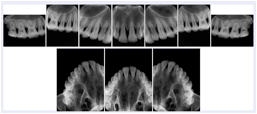

Intra-oral radiography typically involves acquisition of multiple images of various parts of the dentition. Many digital radiographic systems offer customized templates that are used for displaying the images in a study on the screen. These templates may also be referred to as mounts or view sets. The Structured Display Object represents a standard method of encoding and exchanging the layout and intended display of Structured Displays. A structured display object created in this manner could be stored with a study and exchanged with images to allow for complete reproduction of the original exam.

3. A dental provider wishes to capture a series of DICOM IO images for the patient’s dentition. The tooth morphology, teeth are divided into molars, premolars, canines and incisors, and a number of images for each jaw. The anatomic information was captured utilizing the triplet of schema. This standard code sequence is based on ISO 3950-2010, Dentistry - Designation system for teeth and areas of the oral cavity.

Every IO image should have anatomic information either through the primary or modifier sequence.

In most standard cases, images are oriented in structured layouts. These structured displays are useful to be shared between providers for reference purposes.

Table OO.1.1-1 shows structured display standard templates, where Viewset ID is based on the Japanese Society for Oral and Maxillofacial Radiology (JSOMR) classification provided by JIRA (Japan Medical Imaging and Radiological Systems Industries Association, www.jira-net.or.jp). Expected or typical teeth to be imaged location, region and designation codes are based on ISO 3950-2010, Dentistry - Designation system for teeth and areas of the oral cavity. For all the hanging protocols listed in OO.1.1-1, the value to use for Hanging Protocol Creator (0072,0008) is "JSOMR" and the value to use for Hanging Protocol Name (0072,0002) does not include "JSOMR" (e.g., "DL-S001A", not "JSOMR DL-S001A").